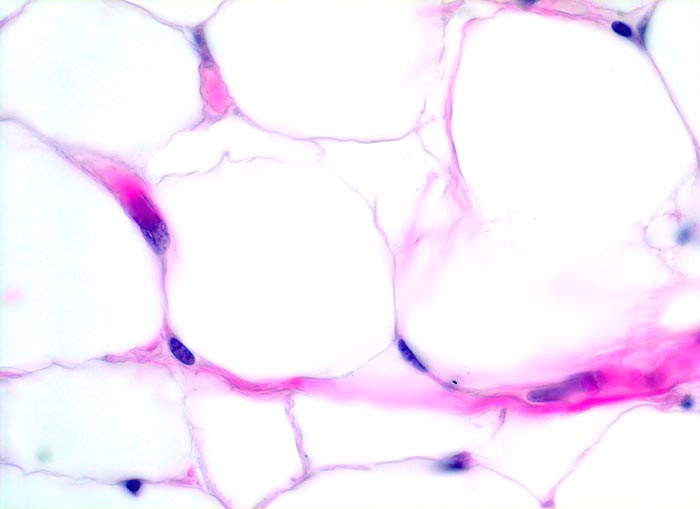

PathoPic ID 4061 - reifes Fettgewebe

reifes Fettgewebe

Normalbefund

Weichteile Rumpf

Weichteile

Reife Fettzellen mit reichlich transparentem Zytoplasma. Das Fett wurde durch die Fixation herausgelöst. Am Rand der Zellen ein schmaler flachgedrückter Kern mit feinem Chromatin.

Histologie

400